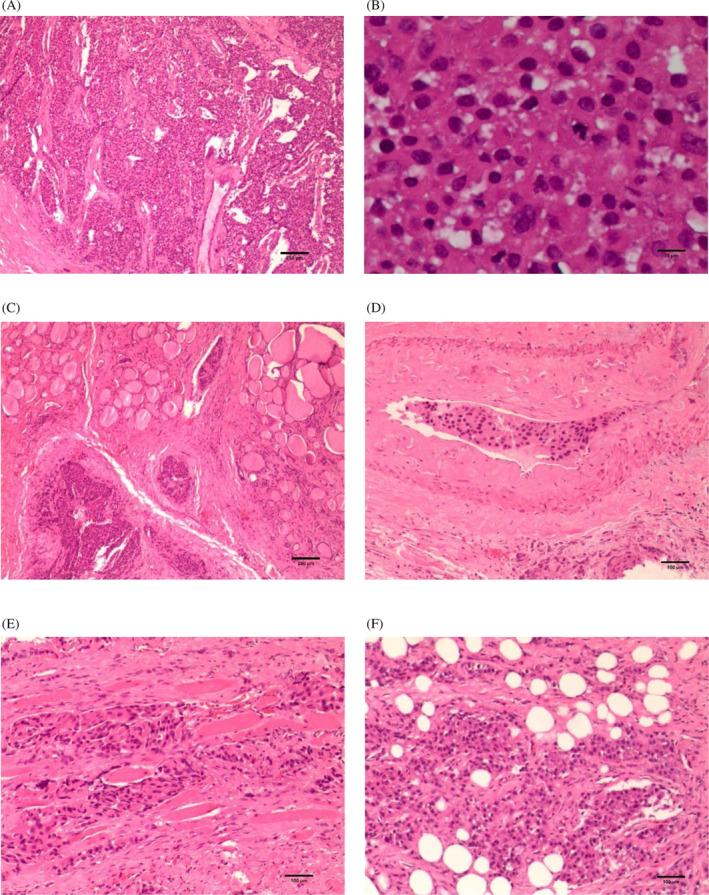

在完成骨扫描等相关检查以排除原发性和继发性骨恶性肿瘤后,于2023年1月18日对左甲状旁腺肿块进行了完全切除。术中发现左侧甲状旁腺肿块侵犯左侧甲状腺叶及其周围组织,冷冻结果被认为是甲状旁腺起源的肿瘤,然后对甲状旁腺肿瘤进行根治性切除 + 移除相关组织结构 + 左甲状腺和峡部切除术 + 左颈部VI区淋巴结清扫。术后病理诊断为PC,无淋巴结转移(0/4)。苏木精和伊红(HE)染色显示PC侵入甲状腺叶、脂肪和横纹肌组织(图3)。免疫组化显示,肿瘤细胞甲状腺转录因子-1(TTF-1)阴性,甲状腺球蛋白阴性,嗜铬粒蛋白A(CgA)阴性,突触素部分阳性,甲状旁腺激素阳性,CD31和CD34(血管表达)阳性,D2-40(淋巴+)阳性,Ki67为10%(图4)。术后给予补钙、补液和口服左旋甲状腺素片。

图3 苏木精和伊红染色:(A)为甲状旁腺癌肿瘤细胞(比例尺=250μm,×40);(B) 肿瘤细胞的核分裂(比例尺=25μm,×400);(C) 甲状腺组织侵犯(比例尺=250μm,×40);(D) 血管侵犯(比例尺=100μm,×100);(E) 横纹肌组织侵犯(比例尺=100 μm,×100);(F) 脂肪组织侵犯(比例尺=100 μm,×100)